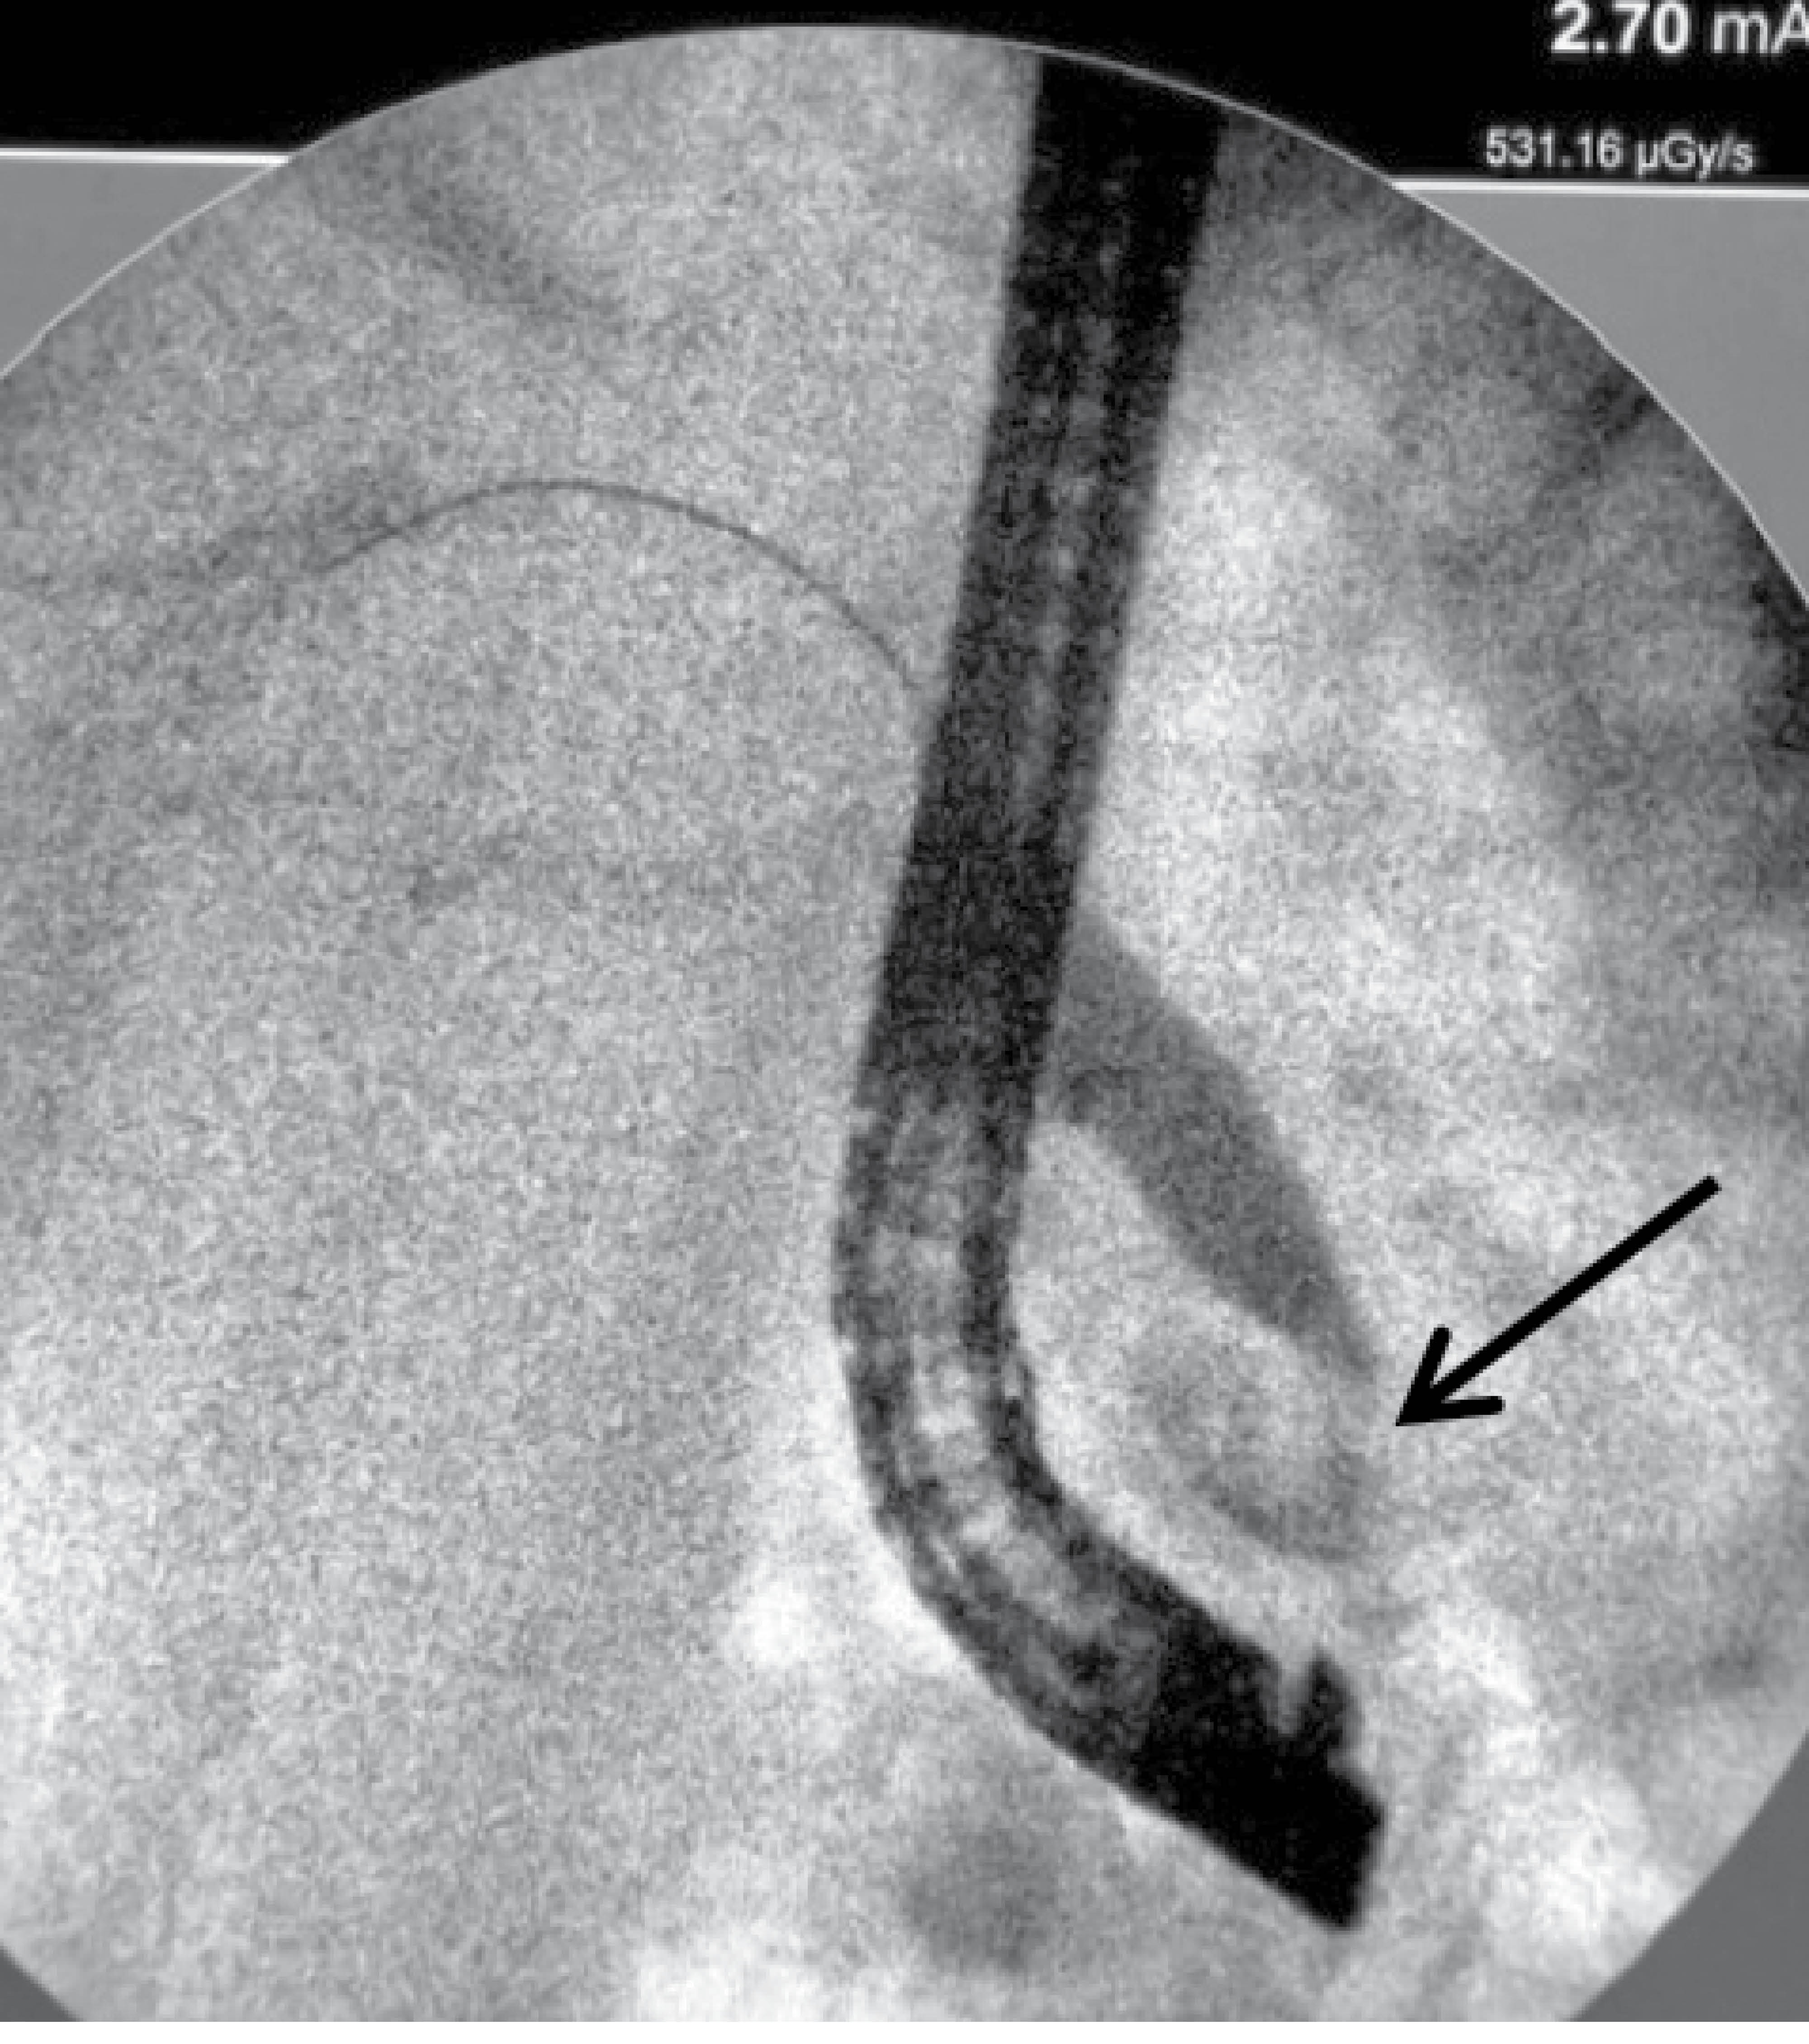

Se decide realizar colangiopancreatografía retrógrada endoscópica (CPRE) con diagnóstico de divertículo yuxtapapilar de 2 × 2 cm de diámetro, divertículo duodenal a 5 cm de la papila hacia la tercera porción duodenal. Compresión extrínseca de colédoco distal secundaria a divertículo yuxtapapilar (Figura 2).

Figura 2